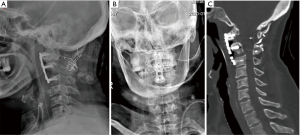

The preoperative anteroposterior open mouth and lateral radiographical images (Figure 1A,B) found the atlantoaxial dislocation and posterior wire fixation. The preoperative CT images (Figure 1C,D) gave us more details of the posterior bony fusion, showed that the bony fusion achieved from the occipital to C4, but the C1/2 fusion is suspected not very stable, one metal wire was transversal walking behind the spinal cord and compress the spinal cord posteriorly, while the upper-posterior of the odontoid process compress the spinal cord anteriorly, very narrow width space for the spinal cord, dura mater and cerebrospinal fluid. The preoperative MR images (Figure 1E,F) also showed the narrow space between the transversal walking wire and upper-posterior of the odontoid process.

However, this patient had undertaken a posterior wire fixation and fusion 20 years ago, the pre-operative CT (current operative time) images showed that one metal wire was transversal walking through behind the spinal cord and compress the spinal cord posteriorly (Figure 1C,D). There had amount of bony fusion at posterior region of the occipital to C4, any operation attempt to remove this wire-bone complex construction will have high risk of push the transversal walking wire anteriorly to increase the spinal cord compression, and also increase the instability of this region. Therefore, the anterior decompression will the better choice than posterior approach for this case.